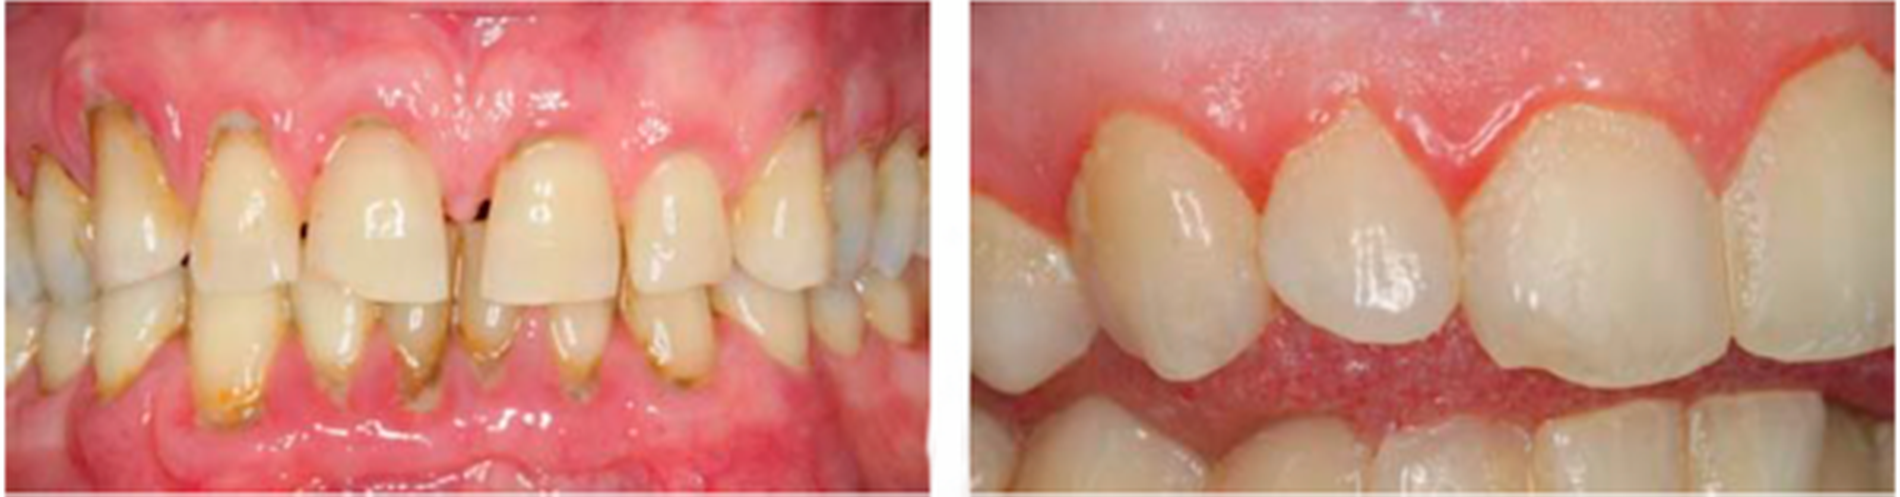

Es stellt sich nun die Frage, ob diese gesamtsystemischen Einflüsse auch Einfluss auf das Parodont haben? Eine interventionelle Pilotstudie an der Uniklinik Freiburg konnte zeigen, dass Probanden unter einer antientzündlichen Ernährung signifikant weniger gingivale und parodontale Entzündungen aufwiesen im Vergleich zu Probanden, die sich mit einer „normalen“ Ernährung (reich an Kohlenhydraten und gesättigten Fettsäuren) ernährten [Woelber et al., 2016]. Dass diese Ergebnisse nicht nur einen kurzfristigen Einfluss auf orale Entzündungsparameter haben, sondern auch signifikant mit einem geringeren Risiko an Zahnverlust einhergehen, konnten auch Kotsakis et al. [2017] in einer Querschnittstudie zeigen. Die Analyse der NHANES(National Health and Nutrition Examination Surveys)-Daten von 6.887 Patienten ergab, dass die Patienten mit einer anti-entzündlichen Ernährung durchschnittlich 0,84 Zähne weniger verloren hatten als Patienten mit einer pro-entzündlichen Ernährung. Weiterhin gibt es zahlreiche Studien, die einzelne Ernährungskomponenten in Bezug zur parodontalen Entzündung untersucht haben (zum Beispiel Zucker, gesättigte Fettsäuren, Vitamine). Diese sollen unter den spezifischen Nährstoffen aufgeführt werden.